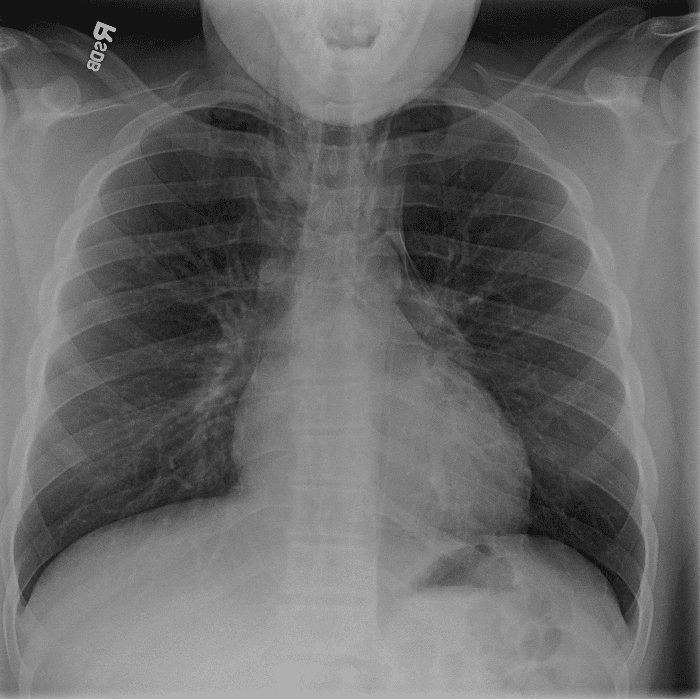

Practice Cases